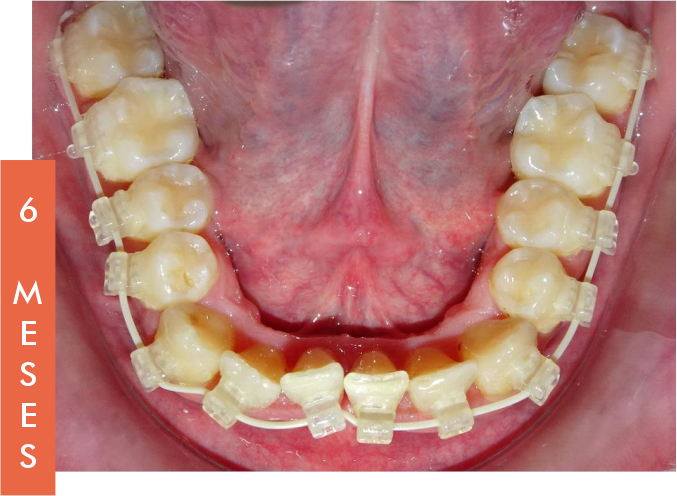

La BTM permite restaurar el Arco Natural Dentoalveolar, mejorando notablemente la estética dental y facial del paciente. Esta filosofía busca devolver una oclusión funcional y estable, respetando la anatomía natural.

Los segundos molares superiores, clave en esta técnica, se mantienen protegidos de fuerzas externas, sirviendo como punto de referencia para lograr una expansión transversal eficaz y controlada.

Esto convierte a la BTM en una herramienta esencial para tratamientos que respetan la biología del paciente.